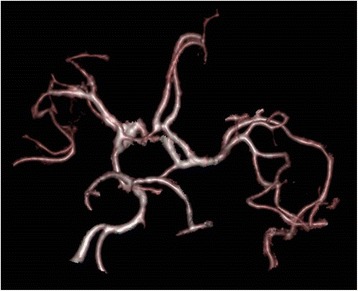

Fig. 4.

Magnetic resonance imaging vascular volume rendering reconstruction obtained from the 3D-T1 gadolinium sequences. Absence of proximal vascular stenosis nor thrombosis

Our patient had multiple ischemic brain lesions located in various vascular territories, which may correspond to cerebral vasculitis. Routine MRI protocol procedures initially performed did not include angiographic sequences. Retrospectively, volume rendering (VR) 3D-vascular reconstructions were performed with the T1 gadolinium sequences revealing no sign of proximal vascular stenosis nor thrombosis (fig. 4). Considering the patient was under curative anticoagulant therapy (for his atrial fibrillation), embolic strokes were here ruled out and infectious vasculitis was considered as highly probable. Such complication is relatively common during the course of pneumococcal meningitis (incidence of 9.8% in a retrospective multicentric study of 162 patients [14]). In contrast, to our best knowledge, no case of meningococcal cerebral vasculitis in adults has been published so far, while one case has been recently reported in a child [15].